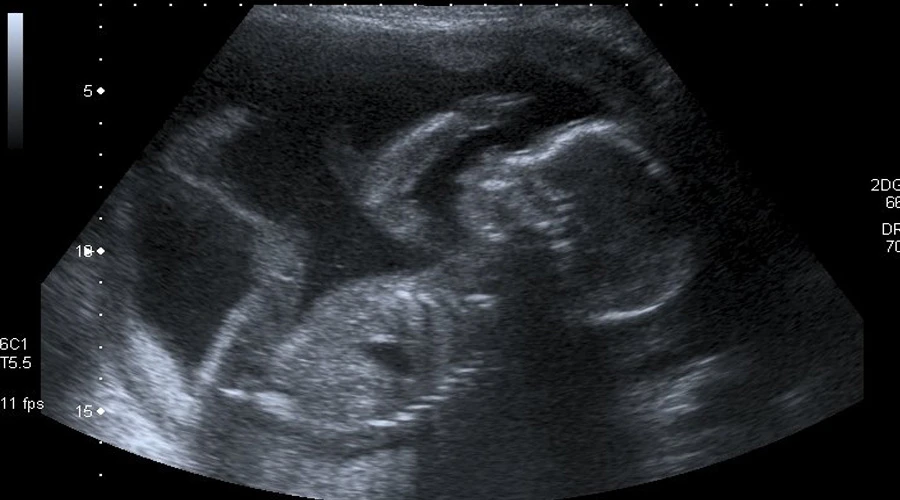

En diciembre de 2011, se practicó al aborto a la embarazada en la clínica El Sur Atocha Clínica Ginecológica de Sevilla, mediante una punción. Según precisan, ginecólogo “prescindiendo de las más elementales medidas de precaución que exige pericia médica, practicó la punción sin cerciorarse antes de cuál era el feto enfermo, pinchando el feto sano, error que pudo haber evitado tomando las elementales medidas de comprobación ecográfica de la posición de ambos fetos”.

Según los datos que aporta el diario ABC, en enero de 2012, en el hospital Puerta del Mar de Cádiz, se descubrió mediante una ecografía, que la punción había sido practicada ‘al feto sano’.